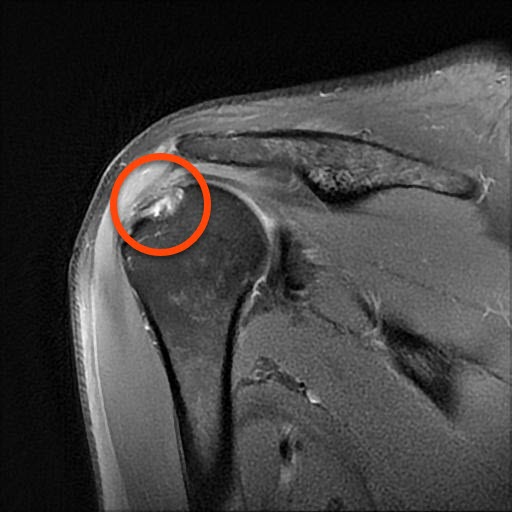

Das ist ein Bild meiner rechten Schulter. Wahrscheinlich werde ich in nächster Zeit das behandeln lassen müssen. Aber in Anbetracht der Tatsache, dass ich in der rechten Hand eine Sensibilitätsstörung habe, auf dem rechten Auge auch nicht gut sehe, stellt sich die Frage ob ich nicht auf die andere Hand umstelle und dann mit links werfe. Mit der Computermaus arbeite ich auch schon immer mit der linken Hand.